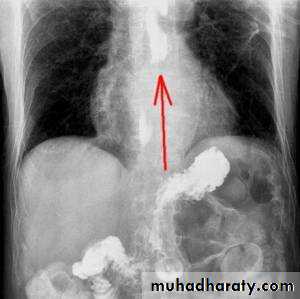

5. barium swallow which shows reflux of the gastric content to the esophagus.